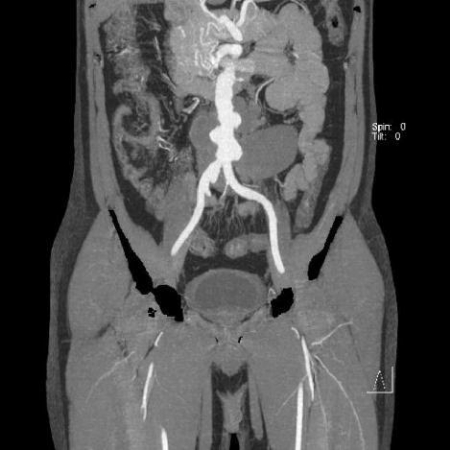

• سی تی اسکن شکم. این آزمایش از اشعه ایکس برای ایجاد تصاویر مقطعی از ساختارهای داخل ناحیه شکم استفاده میکند. میتواند تصاویر واضحی از آئورت ایجاد کند. این آزمایش همچنین میتواند اندازه و شکل آنوریسم را تشخیص دهد.

در طول برخی اسکنهای CT و MRI، ممکن است مایعی به نام کنتراست از طریق رگ تزریق شود تا رگهای خونی در تصاویر واضحتر دیده شوند.